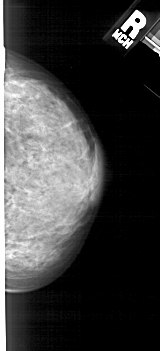

A_1897_1.RIGHT_MLO

RIGHT_MLO LINES 5491 PIXELS_PER_LINE 2386 BITS_PER_PIXEL 12 RESOLUTION 43.5 NON_OVERLAY